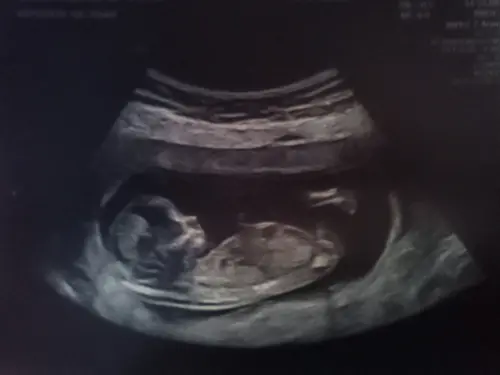

Nu ben ik ook nog geen 13 weken, ik ben 12+4 vandaag. Maar werd automatisch ingepland. Had vorige week mijn termijnecho.

Stond er van te kijken hoe groot het verschil was tussen een week geleden en nu.

Bovenste was vorige week. Onderste nu